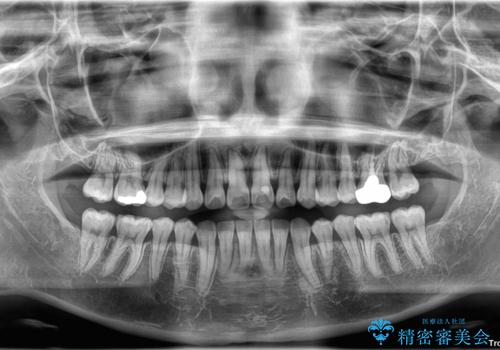

矯正治療期間はわずか10か月と、比較的短期間で終了しました。

前歯のデコボコがなくなり、見た目の印象が大きく変わっただけでなく、歯磨きがしやすくなり、むし歯や歯周病のリスクが大きく減少しました。